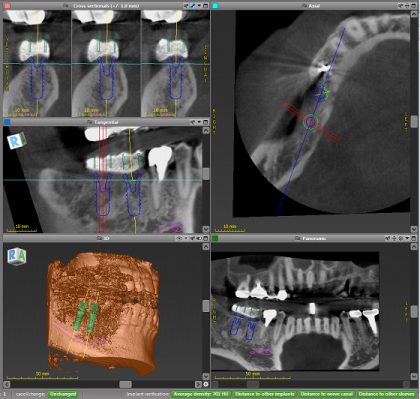

術前にCT検査を行い、理想的なインプラント位置をシミュレーションして手術を行います。

シミュレーションした位置、角度、深さからズレがない様に、すべての手術で専用のサージカルガイドを導入していますので、高精度なインプラント治療が可能です。

インプラント周囲に必要な骨の幅や、隣の歯との適切な位置関係などには、科学的な裏付けのある決まりがありますので、術前のCT撮影は高精度な治療をするのに有用です。

また、場所によっては危険な神経、血管の走行部位に近い場合もあるため、サージカルガイドによって位置、角度、深さをシミュレーションした位置に高精度で手術することは、インプラントが長持ちするだけでなく、神経、血管を損傷するリスクを少なくします。